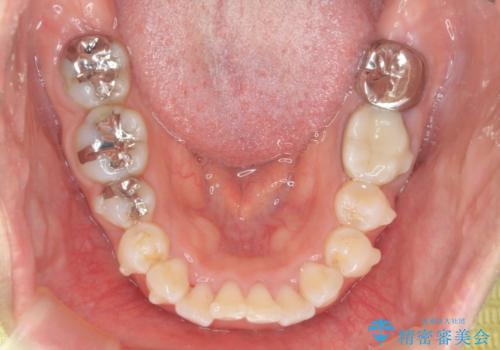

前歯の角度を改善するマウスピース矯正

- 前歯の角度・重なりの改善を求めて矯正治療を希望され来院されました。

通常このような場合、小臼歯を4本抜去しワイヤー矯正を行う治療計画も検討されますが、今回は側方に拡大できる骨量が十分に存在したため抜歯をしない矯正治療の計画を立てます。

しっかりと拡大を行い、IPRも併用したことで歯並びと前歯の角度を大幅に改善することができました。